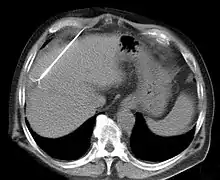

CT scan showing radiofrequency ablation of a liver lesion

RFA may be performed to treat tumors in the lung,[7][8][9] liver,[10] kidney, and bone, as well as other body organs less commonly. Once the diagnosis of tumor is confirmed, a needle-like RFA probe is placed inside the tumor. The radiofrequency waves passing through the probe increase the temperature within tumor tissue, which results in destruction of the tumor. RFA can be used with small tumors, whether these arose within the organ (primary tumors) or spread to the organ (metastases). The suitability of RFA for a particular tumor depends on multiple factors.